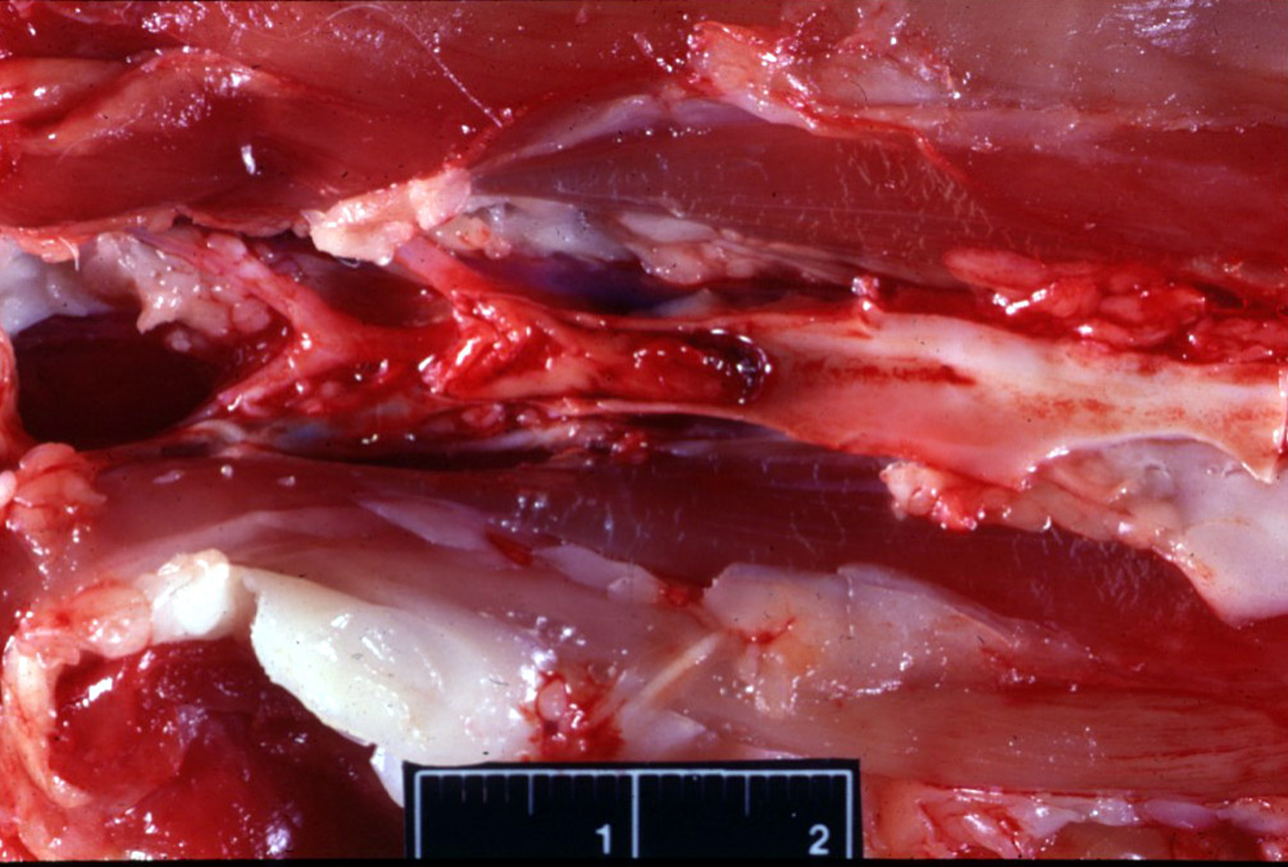

What is being shown here? What caused this?

Vascular damage & development of phlebitis & thrombosis jugular vein (horse) —> IV injections of irritant solutions or intimal trauma produced by IV catheters